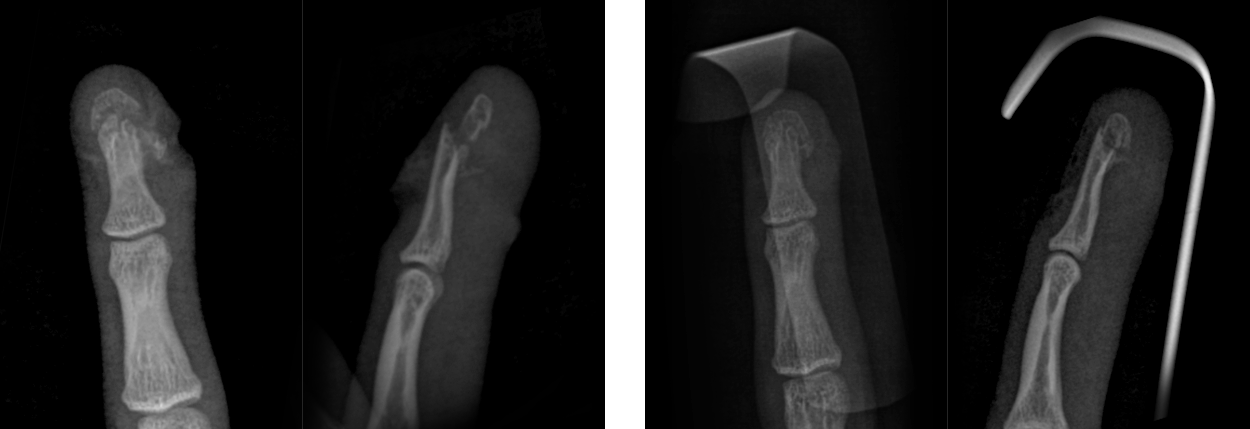

봉합술 후 핀 고정 없이도 골절편이 맞춰진 모습

* 환자에게 받은 소중한 자료입니다.